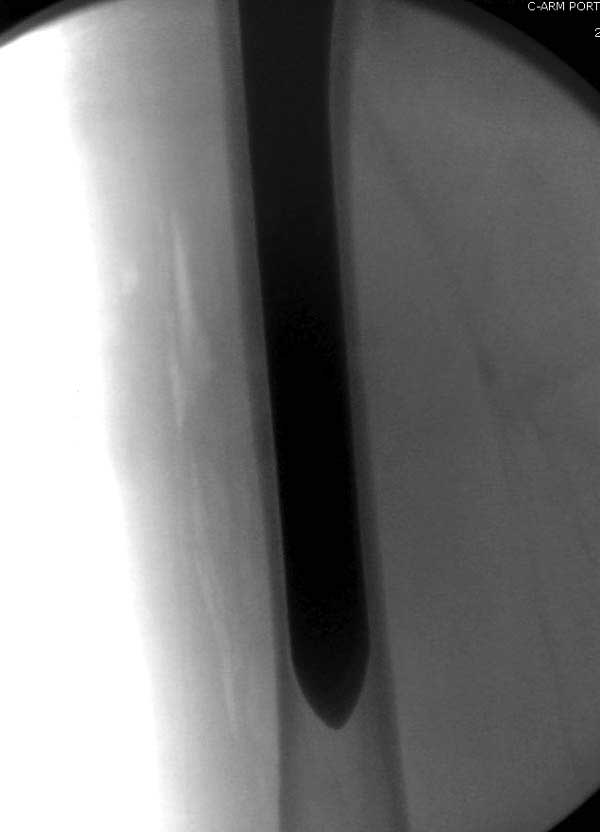

Сеньоры-пэры ревизировали гвоздем, шуруп поставили по той же дорожке, только поглубже. Да еще и bone graft не пожалели. "Результат" уже был через 2 дня.

Если сохранять головку - думаю надо было в валгусе фиксировать перелом гвоздем, или DCS, т.к. все-равно разрезали, чтоб достать DHS.